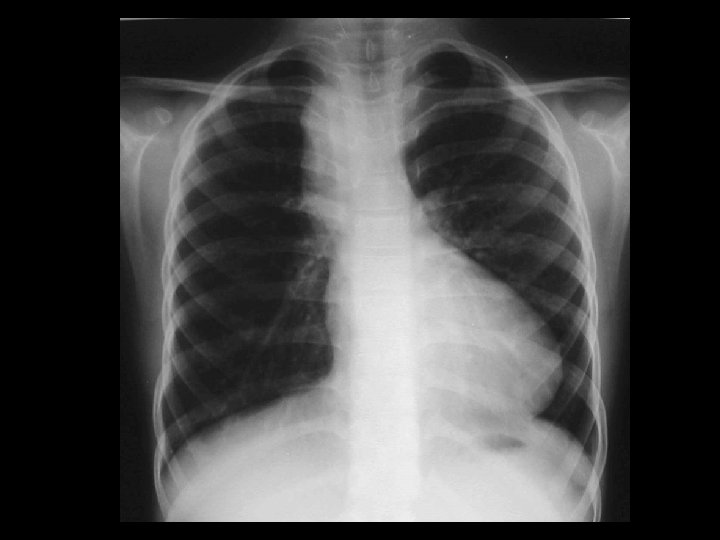

Left hydropneumothorax • Findings: – left pnuemothorax – left pleural effusion (possibly blood) • causes: – penetrating trauma – iatrogenic – bronchopleural fistula